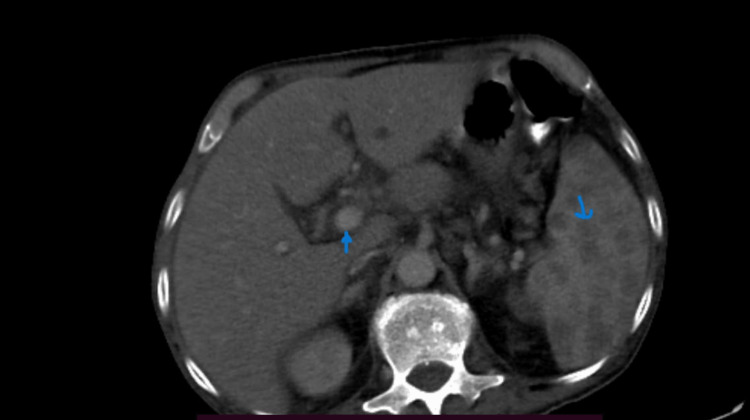

A 32-year-old male, diabetic and chronic alcoholic, came with complaints of pain in the abdomen and fever for 15 days. On examination, there was tenderness in the right hypochondrium. On evaluation, ultrasonography revealed multiple hypoechoic lesions in segment VI of the liver likely abscess, one of which was aspirated and sent for culture. CECT of the chest and abdomen also revealed multiple abscesses in the liver and multiple infarcts and abscess in the spleen (Figure 7), along with cavitary consolidation of the right middle lobe of the lung, with bilateral pleural effusion. Culture of aspirated pus grew B. pseudomallei sensitive to meropenem. The patient started on meropenem and improved over the course of 10 days. The patient was dischaged on oral cotrimoxazole for the next three months.

Figure 7. CT abdomen image showing multiple liver abscesses, splenic abscesses, and splenic infarcts in the coronal section.